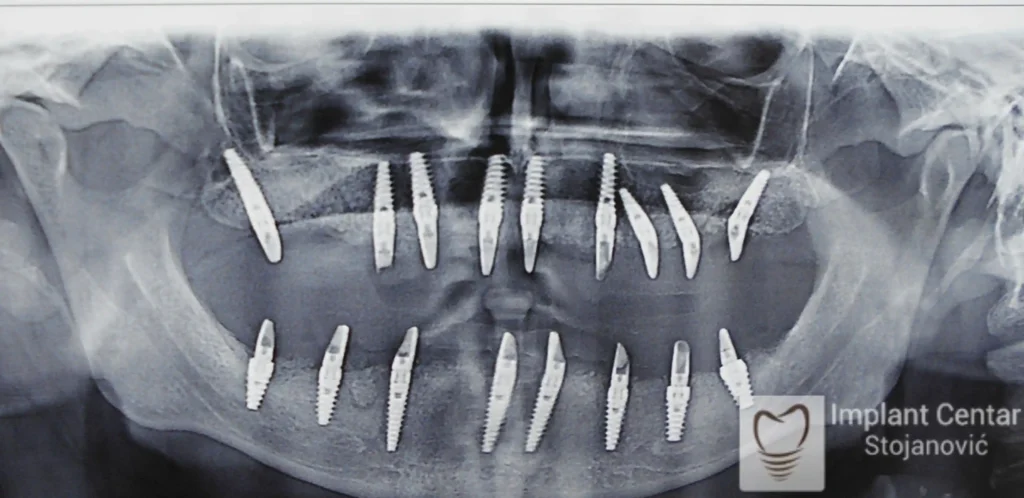

Zbog toga je plan terapije uključivao vađenje svih preostalih zuba i ugradnju implantata u gornjoj i donjoj vilici. U gornjoj vilici postavljena su i dva tuberopterigoidna implantata, kao zamena za sinus lift proceduru, što se može videti na ortopan snimku nurađenom odmah nakon ugradnje (slika 3).

Već tri dana nakon operacije, pacijent je zbrinut fiksnim privremenim zubima na implantatima, čime je odmah povraćena funkcija i estetika osmeha.